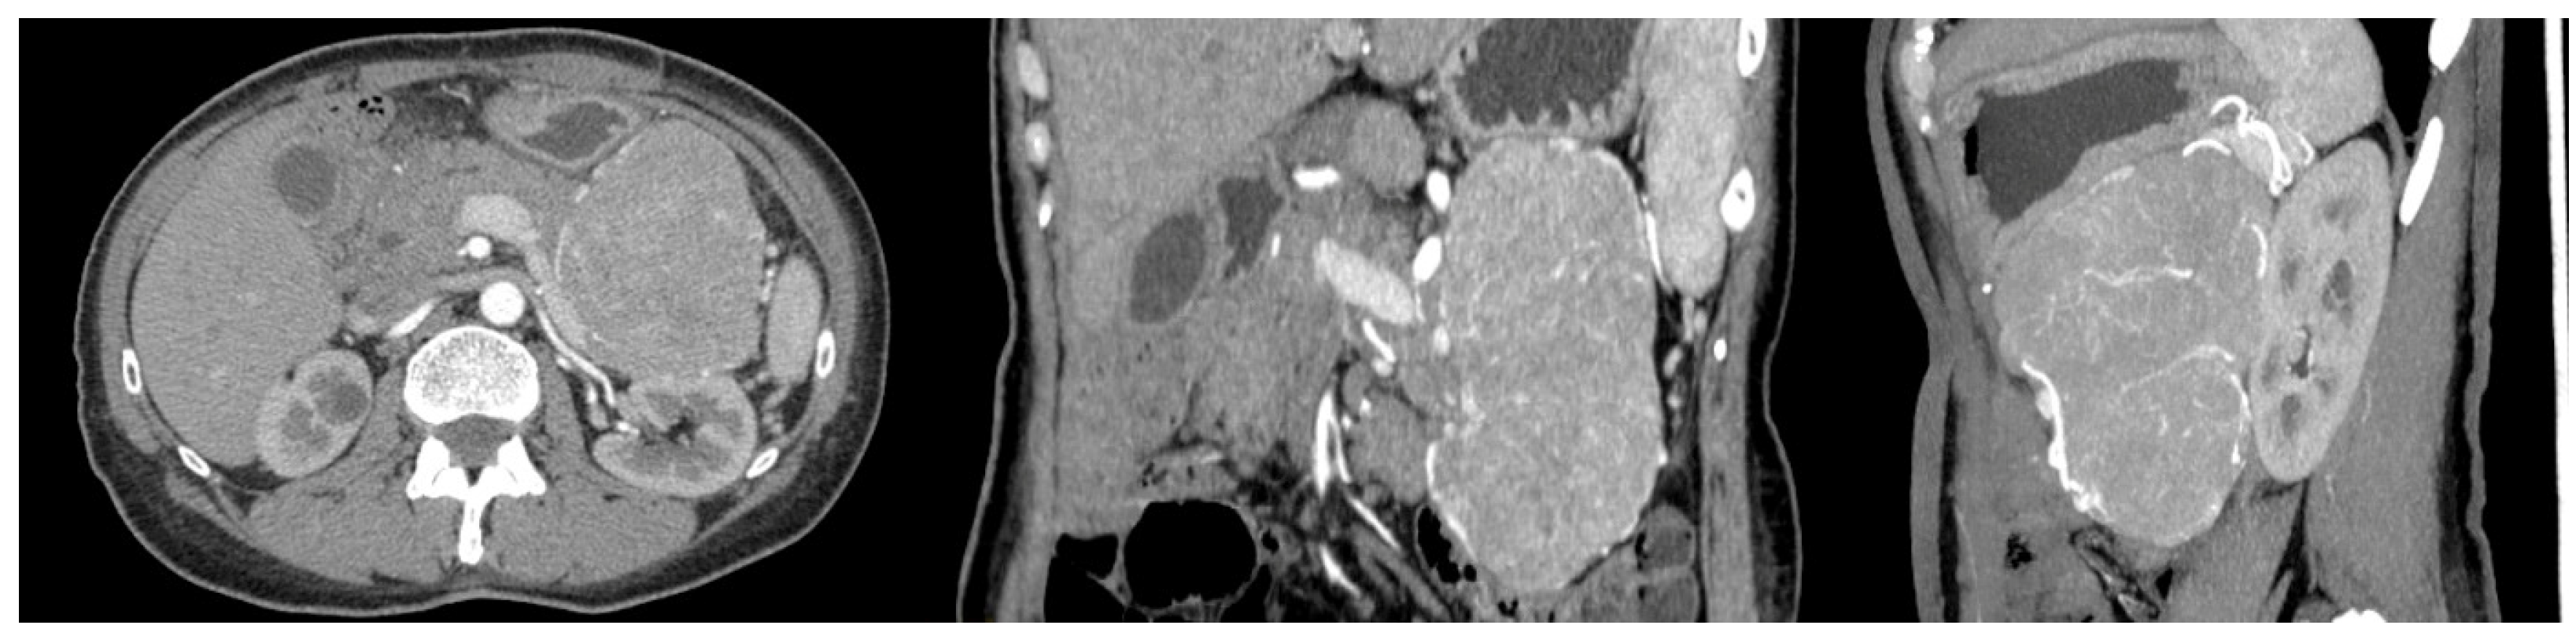

A 56-year-old woman with FAP was admitted to the University Hospital of Padua, complaining of dyspepsia and upper abdominal pain. She was a carrier of a deleterious transversion C to A at nucleotide 2805 of the APC gene, causing a premature stop codon and resulting in a truncated protein (Y935X). Her medical history revealed that she underwent a total colectomy with low ileorectal anastomosis at the age of 21 due to extensive colonic polyposis. Subsequent regular surveillance revealed no extracolonic manifestations except for gastric fundic gland polyps and duodenal adenomas. Some 35 years after colectomy, clinical examination suggested a mass in the left hypochondrium. This suspicion was confirmed by a CT scan, which showed a well-defined retroperitoneal mass measuring 19 × 8.5 cm. The mass originated from the tail of the pancreas with no evidence of nodal or distant metastases (Figure 1). The patient underwent a radical distal splenopancreatectomy. Histologically, the neoplasm showed acinar differentiation with squamous nests and strong, diffuse cytoplasmic and nuclear β-catenin staining (Figure 2). Systemic therapy was not recommended, and the patient remains alive with no evidence of local recurrence or distant metastases exceeding 100 months of follow-up.

Figure 1.

CT scan of the case report.